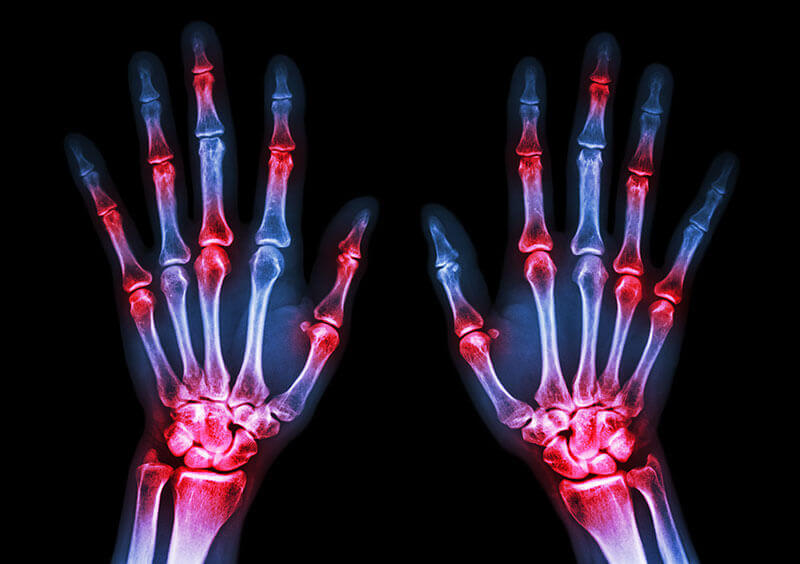

Factor reumatoid crescut tratament. Un titru crescut de fr poate fi dat de o serie de afecțiuni autoimune și de o serie de infecții severe. Titru 1 640 iarasi crescut. Cand sunt prezenti autoanticorpi exista un risc crescut de boala mai severa si deformanta. Poliartrita reumatoida provoaca leziuni articulare la 80 pana la 85 dintre pacienti iar leziunile apar in primii 2 ani de boala.

Factorul reumatoid este astfel un complex proteic care se poate comporta fie ca un izoanticorp fie ca un heteroanticorp. Un titru crescut al factorului reumatoid poate fi dat de o serie de afectiuni autoimune inclusiv artrita reumatoida si de o serie de infectii severe. Lasata netratata riscul de mortalitate este crescut. Fara un tratament adecvat durerea cronica dizabilitatea si afectarea grava a vietii normale sunt rezultate nefericite ale acestei boli.

In tabelul de mai jos sunt prezentate alte conditii asociate cu factor reumatoid pozitiv 1 5. Factorul reumatoid fr este o proteina produsa de sistemul imunitar care poate ataca tesuturile sanatoase din corpul tau. Detectarea factorului reumatoid reprezinta unul din criteriile acr american college of rheumatology de diagnostic al poliartritei reumatoide. In mod ocazional o crestere a factorului reumatoid poate aparea si in cazul persoanelor sanatoase.

Titrurile mari sunt mai specifice pentru diagnosticul de artrita reumatoida 5. Fan poate fi pozitiva in pana la 40 din cazuri. Mai putin factorul reumatoid care a iesit mare 85 2 am niste dureri in fesa stanga si o stare generala alterata oboseala chiar si dimineata la trezire stare de agitatie palpitatii de asemenea am de circa o luna de zile o durere de gat continua la inghitire si care nu cedeaza la nimic am facut de doua ori exudat. Acest anticorp este mai specific pentru artrita reumatoida decat factorul reumatoid cu pana la 95 dintre pacientii cu rezultate pozitive cu ar.

Factor reumatoid iga igm. Persoanele sanatoase nu produc aceasta proteina ele nu au factorul reumatoid prezent. Factorul reumatoid este prezent în serul majorităţii pacienţilor cu poliartrită reumatoidă peste 75 din cazuri dar nivelul său poate fi crescut şi în alte afecţiuni reumatice sau procese cronice inflamatorii cum ar fi lupus eritematos sistemic sifilis tuberculoză polimiozită hepatită virală mononucleoză infecţioasă. Am 49 ani si in urma unor dureri la nivelul cotului stang si a unei usoare amorteli a degetelor mic si inelar de la aceeasi mina mi s a recomandat analiza factor reumatoid rezultatul este 127 7 iu ml valoare f crescuta in acelasi timp am facut si anticorpi antinucleari cu rezultatul.